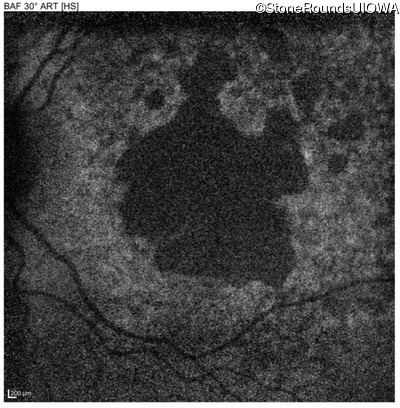

Blue Autofluorescence - Right - 20/32 +2

Exemplar